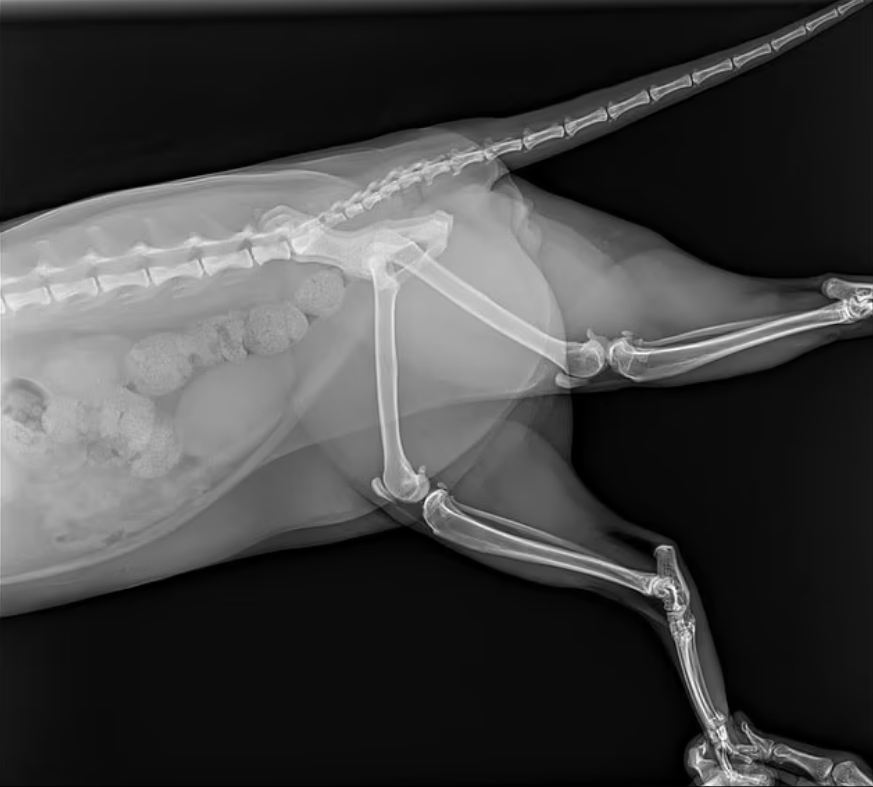

وتم نقل القطة إلى الطبيب البيطري ووجدت أنها مصابة بعدة كدمات ، ومخالب مكسورة ، وأنف منتفخ من الاصطدام بالزجاج ، ولكن لا توجد إصابات تهدد الحياة.